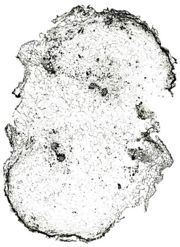

内部形態の比較(市場品)

浙江省産市場品の横切面では、形成層は明瞭で環状につながっている。道管は形成層の近くに散在しており、中央に髄がある。コルク層を表面視するとコルク細胞は厚膜の長条形である。 韓国産市場品の横切面では、維管束が放射状に配列し、形成層は不明瞭で放射組織によって分断され、環状につながらない。コルク層を表面視すると、コルク細胞は薄膜の多角形である。

部位による内部形態の比較 ①

兵庫県柏原における試験栽培品(浙江省産を種付け)は浙江省市場品と同様の形態を呈していた。 <横切面> ・形成層は明瞭で環状につながる。 ・道管は形成層の近くに散在している。 ・中央に髄がある。

| ○試験栽培品 (種塊茎/親) |

○試験栽培品 (新塊茎/子) |

○試験栽培品 (塊茎間) |